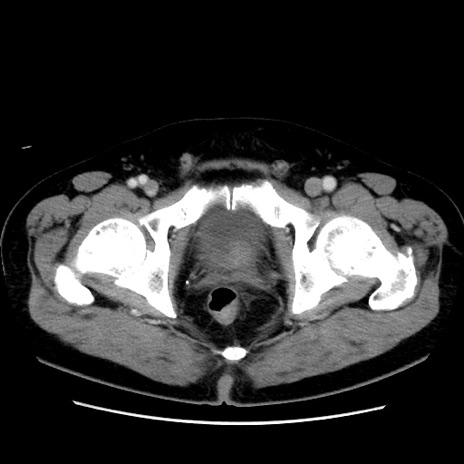

症例16(横断像)

【症例】 70歳代男性

【主訴】 腹痛、嘔吐

【現病歴】 約1ヶ月前より間欠的に腹痛と嘔吐あり、当院消化器内科を受診したところCTで多発する肝臓のLDAを指摘され、精査中であった。以降は消化器症状は安定していたが、2日前より嘔気と腹痛があり、同日より排便・排ガスが消失した。改善認めず、 本日、救急外来を受診した。

【既往歴】 大腸ポリープ切除後。

【身体所見】意識清明・会話良好、BT 36.3℃、BP 127/80mmHg、 P 80bpm、腹部:膨満あり、平坦・軟、上腹部正中および下腹部正中に圧痛あり、反跳痛なし、筋性防御なし。

【データ】WBC 7200、CRP 0.77